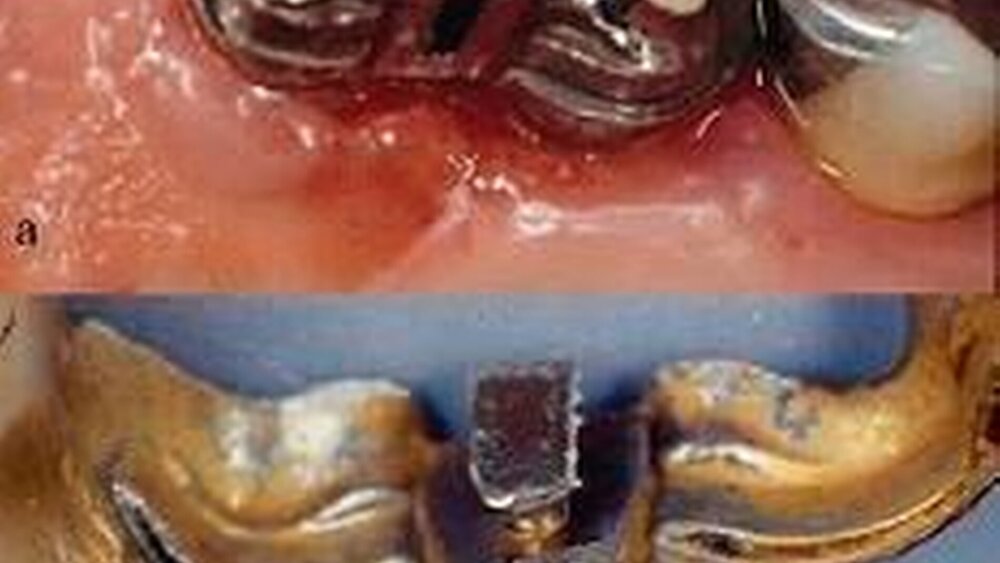

Fall 2

(Abbildung 11) zeigt eine entzündete Schleimhaut im Oberkiefer, verursacht durch die korrodierende Lötstelle zwischen dem Prothesengewebe (Co-Basislegierung) und der hochgoldartigen Brücke. Die metallurgische Zusammensetzung des korrodierten Lotes (neun verschiedene und zum Teil toxische Metalle) lassen sich in der entzündeten Schleimhaut in unphysiologischem Maße wieder auffinden.